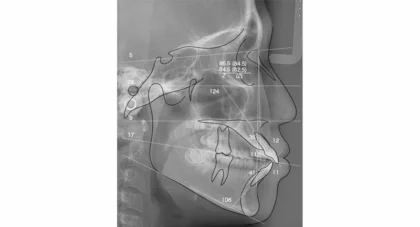

矯正治療の効果を最大限に引き出すには、正確で綿密な診断が欠かせません。当院では、セファロレントゲンや歯科用CTに加え、AIを活用したデジタル診断で歯並びや噛み合わせを精密に把握し、治療後のシミュレーションも行います。一般的な歯科医院では行われない軟組織分析や気道評価にも対応し、骨格や顔貌のバランスまで考慮。必要に応じて医科と連携した精密検査も取り入れることで、より総合的で安全な治療計画を立案しています。

硬組織分析・軟組織分析

横顔のバランスや唇の位置、顎のラインなど、見た目の美しさや自然な表情に関わる部分を評価。笑ったときの印象や横顔のシルエットまで考慮することで、より自然で調和のとれた仕上がりを目指せます。硬組織分析

骨格のズレやバランス

軟組織分析

唇や顎の位置

気道評価

睡眠時無呼吸症候群などのリスクも確認し、呼吸機能に配慮した治療計画を立てます。